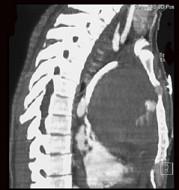

男,33岁,右胸部外伤,胸闷、气短,结合CT图像,最可能的诊断是 ( )A、淋巴管瘤B、淋巴瘤C、纵隔血肿D、畸胎瘤E、胸腺瘤

问题 男,33岁,右胸部外伤,胸闷、气短,结合CT图像,最可能的诊断是 ( )

选项 A、淋巴管瘤 B、淋巴瘤 C、纵隔血肿 D、畸胎瘤 E、胸腺瘤

答案 C